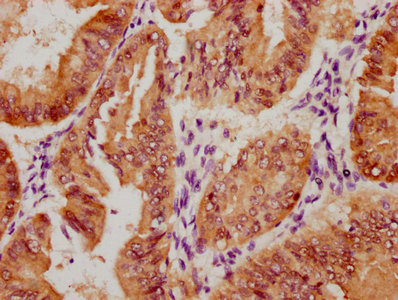

IHC image of CSB-PA892485ESR1HU diluted at 1:50 and staining in paraffin-embedded human endometrial cancer performed on a Leica BondTM system. After dewaxing and hydration, antigen retrieval was mediated by high pressure in a citrate buffer (pH 6.0). Section was blocked with 10% normal goat serum 30min at RT. Then primary antibody (1% BSA) was incubated at 4°C overnight. The primary is detected by a Goat anti-rabbit polymer IgG labeled by HRP and visualized using 0.05% DAB. Secondary antibody only control: uses 1% BSA instead of primary antibody